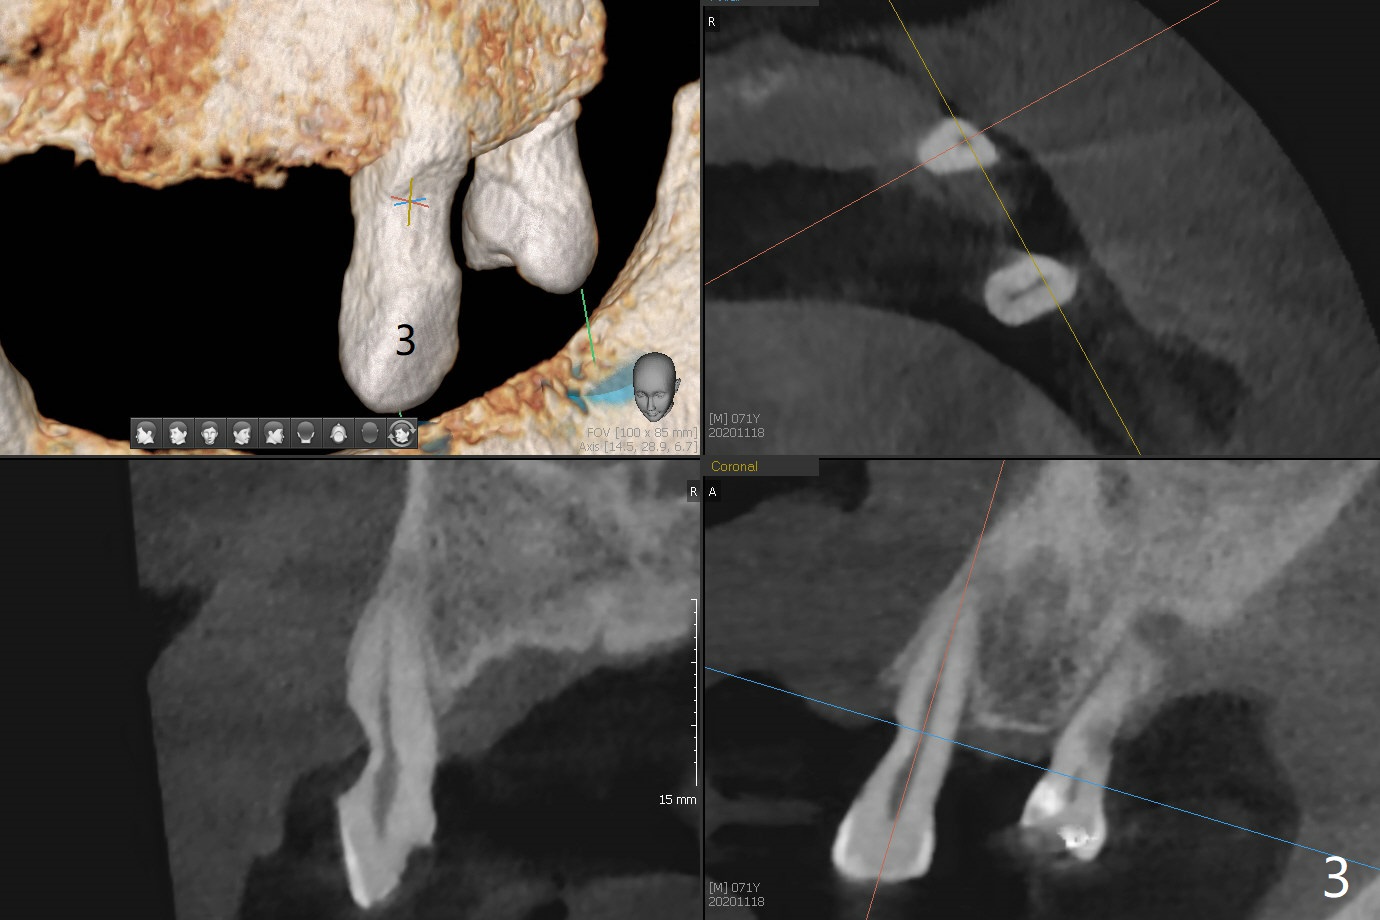

71岁男主诉下颌局部托牙松动(图一),侧切牙不适,临床检查显示后者有咬合创伤,局部卫生不佳,对策:洗牙以及左下4,6植入植体,放置带有球的基台(图五,六)。上颌局部托牙有三个自然牙,挺稳定,但是颈部缺损严重,需要修补(图二,三),左上5远中龋齿需要根管治疗(图四),尽量延长基牙寿命。一个月后病人回来却要求处理松动疼痛右下2,不愿意种植,与3固定和调整咬合,症状消失。Return to No Caries Overdentures Xin Wei, DDS, PhD, MS 1st edition 11/18/2020, last revision 12/13/2020